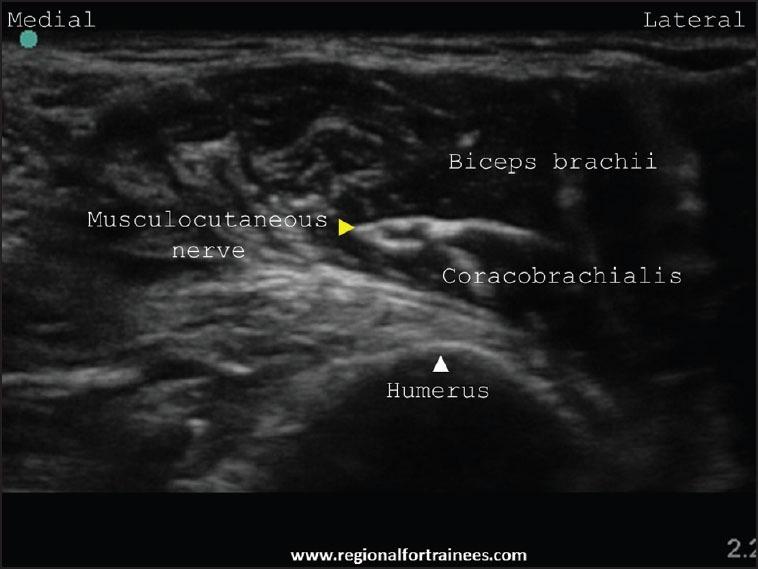

Upper extremity surgery is commonly performed under regional anesthesia. The advent of ultrasonography has made performing upper extremity nerve blocks relatively easy with a high degree of reliability. The proximal approaches to brachial plexus block such as supraclavicular plexus block, infraclavicular plexus block, or the axillary block are favored for the most surgical procedures of distal upper extremity. Ultrasound guidance has however made distal nerve blocks of the upper limb a technically feasible, safe and efficacious option. In recent years, there has thus been a resurgence of distal peripheral nerve blocks to facilitate hand and wrist surgery. In this article, we review the technical aspects of performing the distal blocks of the upper extremity and highlight some of the clinical aspects of their usage.

上肢手术通常在区域麻醉下进行。超声检查的出现使得进行上肢神经阻滞相对容易,且可靠性高。对于大多数上肢远端的外科手术,臂丛神经阻滞的近端入路,如锁骨上神经丛阻滞、锁骨下神经丛阻滞或腋路阻滞,是比较常用的。然而,超声引导使得上肢远端神经阻滞成为一种技术上可行、安全且有效的选择。近年来,远端周围神经阻滞因此再度兴起,以方便手部和腕部手术。在本文中,我们回顾了进行上肢远端阻滞的技术要点,并强调了其使用的一些临床方面。